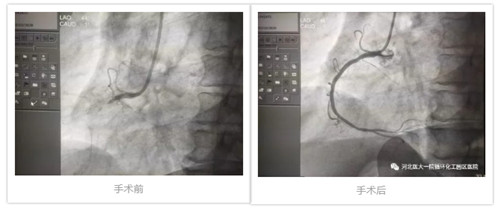

近日,薛阿姨吃過(guò)午飯后,出現(xiàn)腹脹、惡心、嘔吐、腹瀉等癥狀,不能緩解,家人緊急將她送來(lái)我院。入院后,心內(nèi)科迅速為其進(jìn)行相關(guān)檢查,后診斷為“急性心肌梗死”,經(jīng)綜合評(píng)估認(rèn)為薛阿姨要行冠脈造影和支架植入手術(shù)效果更佳。

在醫(yī)大一院心臟中心強(qiáng)大的技術(shù)力量支持下,手術(shù)十分順利,觀察期過(guò)后,薛阿姨返回我院繼續(xù)接受下一步康復(fù)治療。目前恢復(fù)良好,已出院回家。